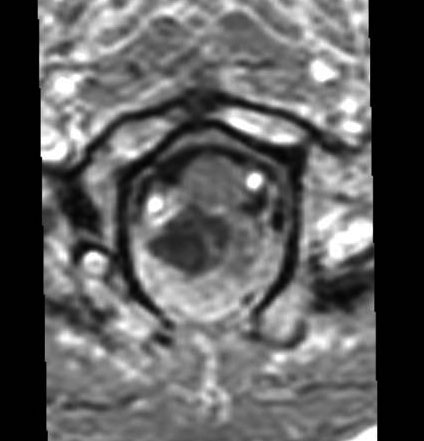

- MRIでみると脊髄の真ん中にあるのが特徴です

- ガドリニウム造影剤で増強されて白く写ります

- 嚢胞を作ったり腫瘍内出血したりします